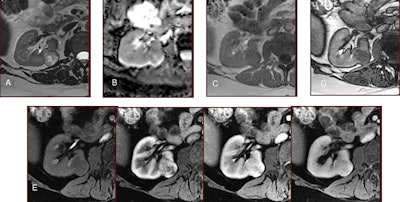

The new mpMRI protocol in play at Bordeaux for differentiation is now being validated for diagnostic accuracy. In the protocol, the most useful sequences for characterization are as follows:

- T2-weighted sequences: These must be performed strictly with turbo or fast spin echo and never in T2-weighted fast gradient echo. This allows the evaluation of the tumor's signal strength compared with the kidney. Only fat-poor angiomyolipoma (fpAML) and type 1 papillary carcinoma have a much lower signal than the kidney.

- T1-weighted gradient-echo sequences with chemical shift (Dixon) imaging: A drop in signal can be seen in opposed-phase in cases of fpAML, clear cell carcinoma, or papillary carcinoma and in in-phase images in cases of papillary carcinoma.

- Diffusion sequences: With these also, only cases of fpAML and papillary carcinoma have a much lower signal than the kidney.

- Dynamic sequences after injection of contrast media allow the "plotting" of enhancement: Only cases of papillary carcinoma show very poor and very progressive enhancement.

Through comparing and combining these different criteria, radiologists can arrive at different, more specific diagnoses, Grenier noted.